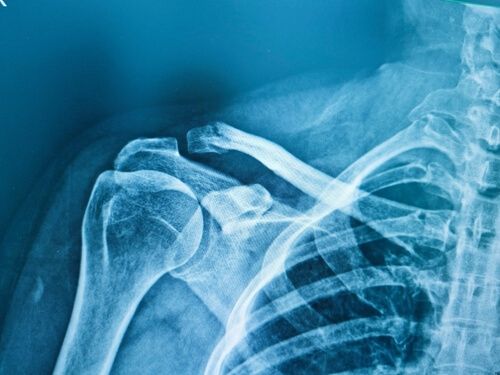

- Röntgenfoto: Auf der Röntgenaufnahme wird die Struktur Ihrer Knochen angezeigt. Dies ist die häufigste Methode zur Diagnose eines Schlüsselbeinbruchs.

- CT-Scan: ein CT-Scan (Computertomographie) zeigt ein detaillierteres Bild der Fraktur.